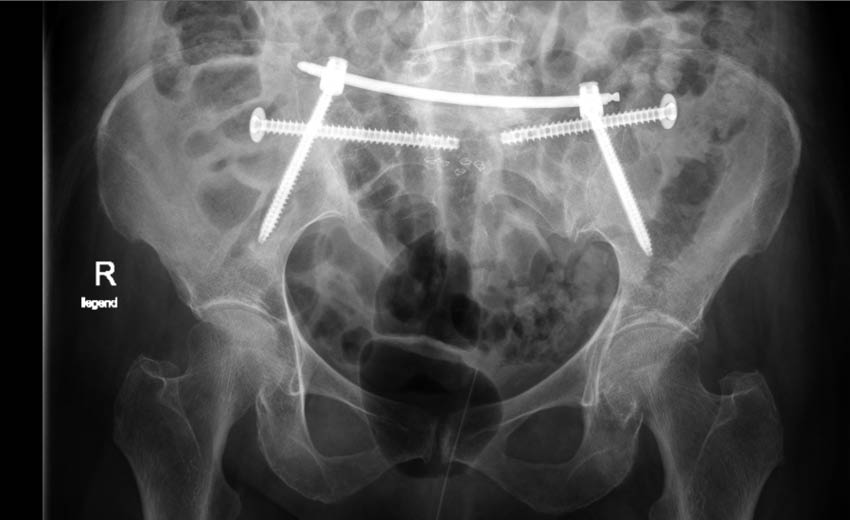

Abb. 4 (oben) : postoperative konventionell radiologische Kontrolle nach percutaner horizontaler Stabilisierung des hinteren Beckenrings beidseits mit Fixateur interne und iliosacraler Schrauben („iliosacrales bridging“) in anterior-posteriorer Projektion

Abb. 4: postoperative konventionell radiologische Kontrolle nach percutaner horizontaler Stabilisierung des hinteren Beckenrings beidseits mit Fixateur interne und iliosacraler Schrauben („iliosacrales bridging“) in anterior-posteriorer Projektion

In der Folge wurden auch Ergebnisse nach Zementaugmentation dieser Fixateuranordnung bei instabilen Fragilitätsfrakturen beschrieben [18]. Es besteht als Modifikation dieser Methode zudem die Möglichkeit, den horizontalen Fixateur zur Versorgung unilateraler Becken-B-Verletzungen einzusetzen. Dies gelingt durch eine Verkürzung der Fixateuranordnung und Platzierung einer Schraube auf der unverletzten Seite des Os sacrum in Höhe des S1-Pedikels. Über das Instrumentarium des Fixateurs besteht zusätzlich die Möglichkeit einer gewissen Kompression im Frakturbereich. Zudem kann sowohl mono- als auch bilateral durch eine ergänzende transiliosakrale Verschraubung („iliosacrales bridging“) [Abb. 3 und 4] die Stabilität weiter erhöht werden [17], wobei durch die horizontal hintereinander liegenden Implantate (iliosacrale Schraube + Fixateurquerträger) die Stabilität gegenüber den weiteren beschriebenen Verfahren nochmals deutlich erhöht sein müsste. Bei relativ neuer Osteosynthesetechnik stehen hierzu jedoch vergleichende Studien noch aus. Das „iliosacrale bridging“ zeigt bei einem von Altersstruktur und Verletzungsschweren gemischten Patientenkollektiv gute Ergebnisse.